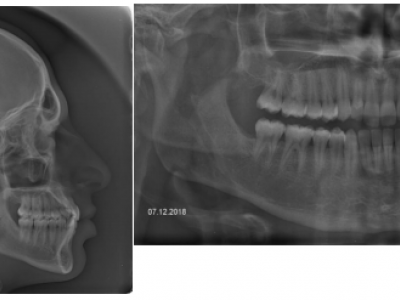

La projection mandibulaire est toujours plus marquée sur la téléradiographie qui est en occlusion (Fig. 11-16), que sur la photo, en position de repos, donc en inocclusion, avec une situation un peu plus reculée de la mandibule. Sur la radiographie panoramique, le manque de place est plus important à l’arcade supérieure, témoignant du manque de développement de cette structure. L’expansion tridimensionnelle de l’arcade donnera de la place aux dents permanentes.

Le patient est revu en denture définitive à 12 ans 9 mois (Fig. 15) avec un bilan radiologique (Fig. 16), pour entreprendre une finition multiattache, les résultats orthopédiques obtenus précocement se sont maintenus.